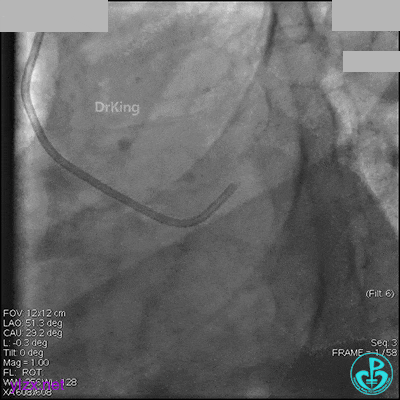

AL 1.0指引导管到位,简单短时尝试导丝不能顺利通过前降支或回旋支病变。改变策略处理右冠脉病变,计划植入2枚支架。AL指引导管到位,Sion blue导丝到达右冠脉远端。导丝通过后1.5mm及2.5mm球囊14~16atm充分扩张中段病变。

右冠脉中段充分扩张后欲植入3.5×38mm支架时,支架难以通过中远段扭曲处,且指引导管、导丝弹出飞扬。反复尝试导丝重新到达右冠脉远端时通过不顺利,局部造影剂滞留,远端血流接近3级。

右冠脉血流3级,患者无症状,终止手术。